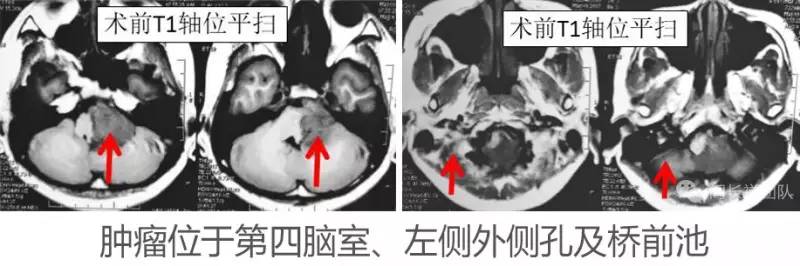

颅底肿瘤手术操作空间狭小,手术难度很大,该部位的室管膜瘤通常位于第四脑室,常常跨过外侧孔朝桥小脑角、桥前池方向生长,肿瘤体积较大时会包绕后组颅神经、面听神经、椎动脉及脑干,大大增加手术难度和风险。手术是治疗室管膜瘤的最佳办法,但是既要全切肿瘤,又要保护好被肿瘤严密包绕的神经血管及脑干,这对神经外科医生提出了很大的挑战!

术前诊断:室管膜瘤(左侧桥前池、桥小脑角、外侧孔,四脑室,颈1椎管)